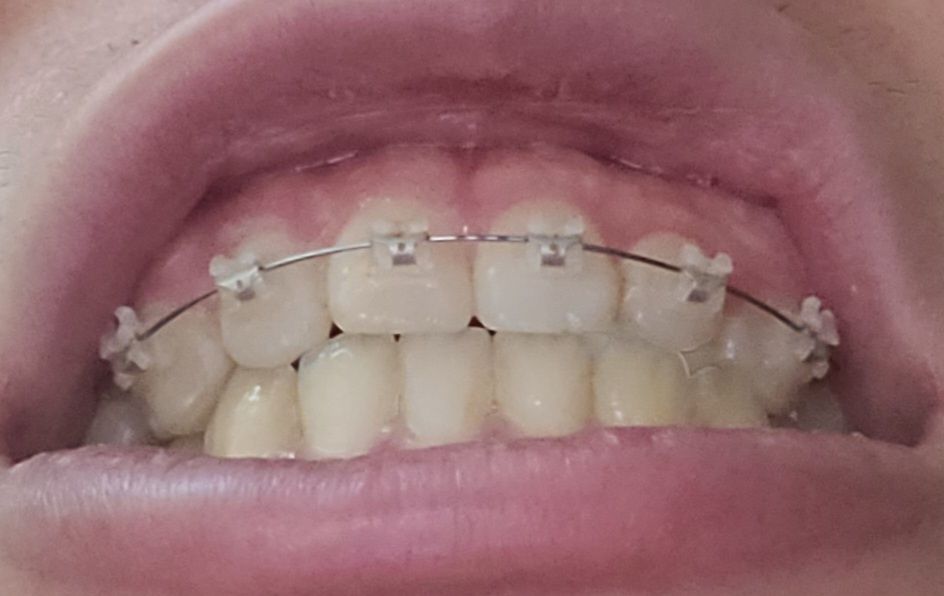

이를 앙 다물고 찍은 사진입니다

절단 교합은 상 하악 앞니가 정확히 일직선으로 맞물려야 합니다. 따라서 지금 정도로 절단교합이라고 하지 않습니다. 또한 음식 섭취 시 앞니는 음식을 간단히 끊는 용도이지 실제로는 어금니가 모든 역할을 합니다. 따라서 해당 치아가 현재로 맞물린다고 해서 마모되지 않습니다. 지금 정도는 교정 중이기 때문에 잘못되었다고 볼수도 없고 절단교합 및 이상이라고 하지 않습니다. 치료를 충실히 받으시길 바랍니다.

절단교합은 위아래 치아의 끝부분끼리 정확하게 맞닿는 상태를 의미합니다.

사진으로는 오른쪽은 절단교합이 아닌 정상교합이며, 왼쪽은 측절치가 애매하게 보이긴 합니다.

말그대로 절단교합은 앞니 끝과 아래니의 끝이 교합이 되는 상태를 말합니다. 사진상으로 보면 절단교합은 아니신거 같아요.